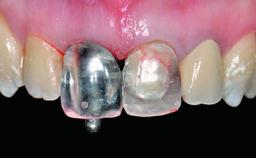

A healthy 37-year-old female patient was referred for a consultation on the replacement of missing tooth 21 with an implant-supported restoration. She stated that several years previously the tooth had been traumatically avulsed following a motor vehicle accident. The tooth was replaced with a three-unit fixed partial denture (FPD) immediately afterwards. Over time, she became disillusioned with the FPD and looked for a different option, including orthodontic therapy. She presented still in her orthodontic appliances, with the pontic sectioned free from the FPD but attached to the archwire. Her orthodontist felt that orthodontic treatment had been successfully completed, but nevertheless referred her before removing the appliances in case adjustments were necessary.